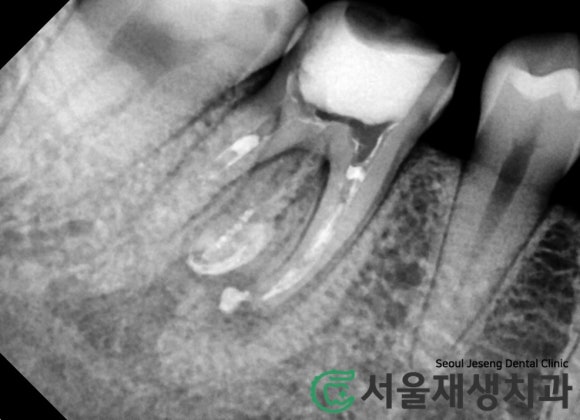

빨간 점선으로 표시된 것 보이시나요?

바로 치료되지 않고 남아있는 뿌리입니다.

어금니에는 신경줄이

여러 개 있기 때문에,

간혹 1~2개를 놓치게 되는 일이 있습니다.

재신경치료를 하게 되는

여러 이유 중 가장 큰 비중을

차지하고 있지요.